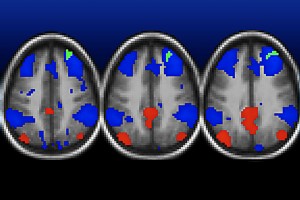

Using a new imaging agent that binds to tau protein and makes it visible in positron emission tomography (PET) scans, scientists at Washington University School of Medicine in St. Louis have shown that measures of tau are better markers of the cognitive decline characteristic of Alzheimer’s than measures of amyloid beta seen in PET scans.